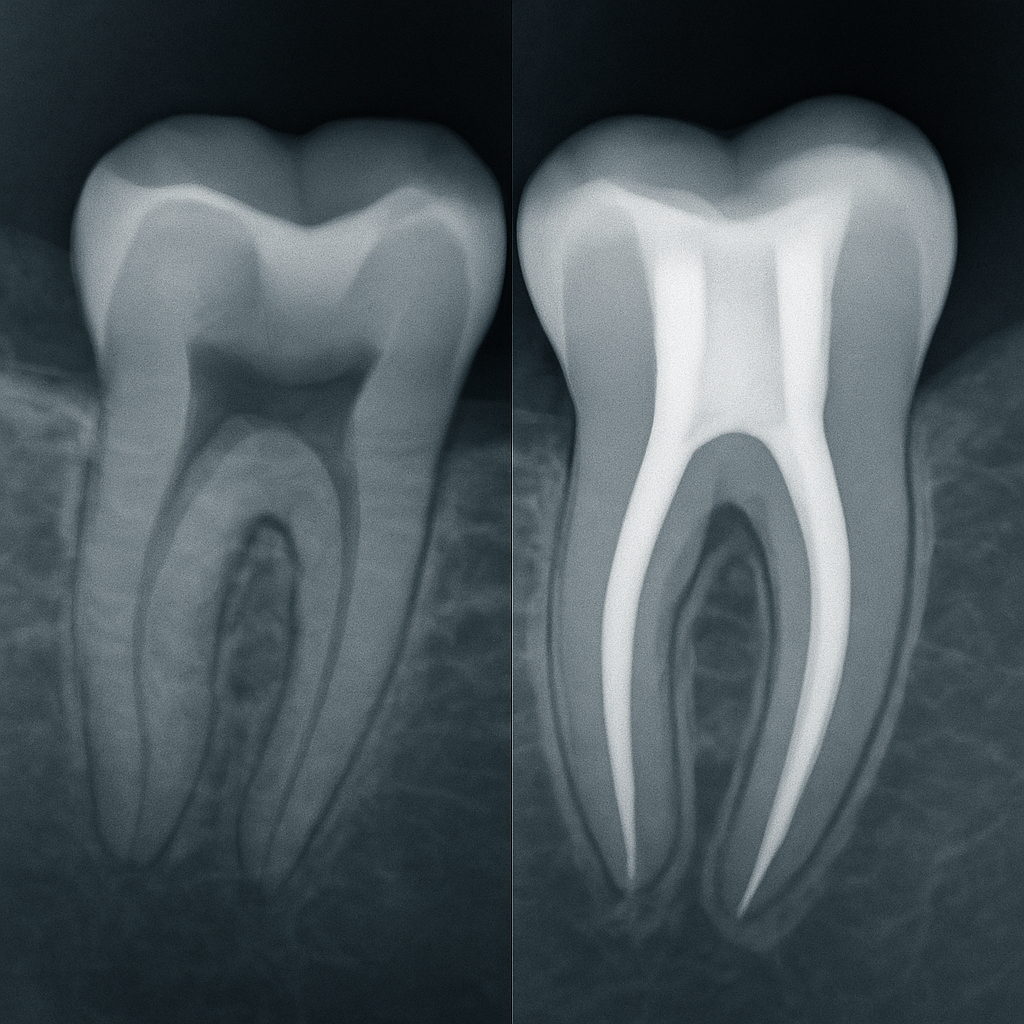

Повторная эндодонтия в практике врача: разбор ошибок и алгоритмы лечения

После курса вы сможете уверенно проводить повторную эндодонтию в сложных клинических случаях: от диагностики и выбора тактики до финальной обтурации и прогноза. Вы научитесь безопасно восстанавливать проходимость каналов, устранять последствия прошлых ошибок, работать с резорбциями, перфорациями и сепарированными инструментами. Это позволит повышать процент сохраненных зубов и принимать обоснованные решения даже в нестандартных ситуациях.

- По данным клинических обзоров, от 20 до 25% ранее пролеченных зубов требуют повторного вмешательства из-за неполной обработки системы каналов, недостаточной изоляции или ошибки на этапе обтурации.

- Наибольшее количество осложнений связано не с техникой пломбирования, а с диагностическими ошибками и неправильным планированием, что становится причиной перфораций, отсутствия доступа к дополнительным каналам и потери проходимости.

- Современные методы ретритмента позволяют сохранить зуб даже при сложной анатомии, резорбциях или наличии сепарированных инструментов, при условии корректной диагностики, адекватной ирригации и контроля инфекций.

- При соблюдении протокола прогноз повторного лечения составляет 85–90%, что делает ретритмент предсказуемой альтернативой имплантации и хирургии.